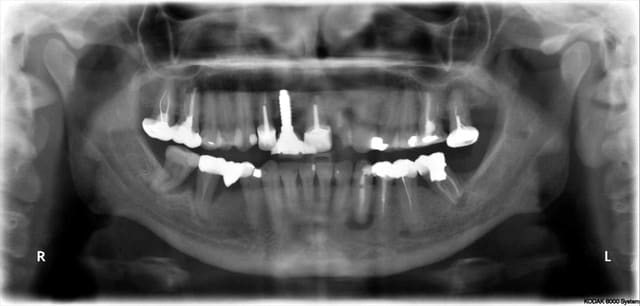

Céramik comme promis Ma réponse en image 2ans après

Est ce l'échec affirmé par certains?

1 Pano du cas

2 Pano qui a déclenché tous ces gentils commentaires

3 Rx le jour de la POSE de la dent

4 La dent le jour de la pose

5 Pano aujourd'hui (le secteur 4 fichu???)

6 Rx aujourd'hui

7 La dent 2ans après

Vos avis!

C'est un implant Léone

L'implant Leone semble donner des résultat interessant.

Pour la pano, les trucs noirs sous les apex, ça ne t'inquiètent pas ? Comme sous la 33 ?

En relisant tout le sujet, on lit qu'effectivement, les kystes de 20 ans , stable ne l'inquiete pas.

Finalement : la paro en secteur 4 : pas mal, pour des dents que beaucoup voulait extraire.